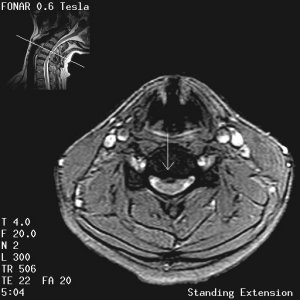

Fonar Stand-Up (TM) MRI Image